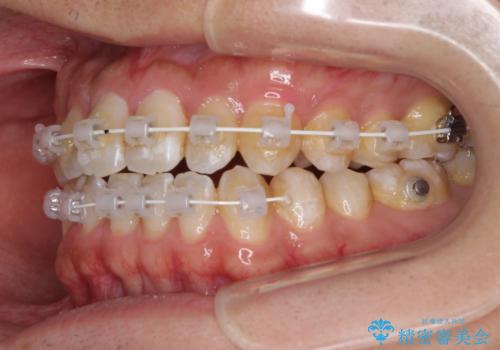

- 矯正装置

- 審美装置

- 上下の前歯の叢生を気にして来院された患者様です。

前歯のみの矯正治療を希望でしたが、上顎臼歯が舌側転位していたため、上顎は全体を、下顎は前歯のみを矯正治療することとしました。

矯正治療は上下全顎を行うことが大前提ですが、費用などの点から、今回は部分矯正を選択することとなりました。

患者様本人は咬みにくさを感じていないようですが、部分矯正は咬み合わせの改善が困難であることが多く、咬みにくさが残ることがあります。